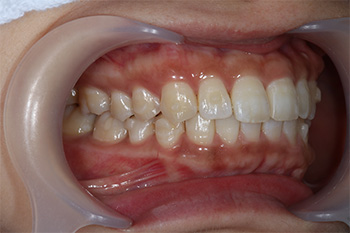

Before

After

| 治療の内容 | マウスピース型矯正装置(インビザライン)による上顎前突の治療(非抜歯矯正) |

|---|---|

| 期間・回数 | 2年4ヶ月・15回(カウンセリング・検査・クリーニング含む) |

| 費用 | 自由診療:マウスピース型矯正装置・インビザライン(800,000円)+専門相談(50,000円)、 総額 850,000円(税込 935,000円) |

| リスク・副作用 |

|